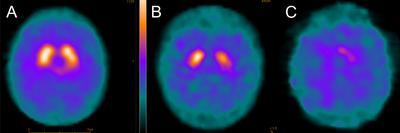

In the first study (https://www.ncbi.nlm.nih.gov/pubmed/23625061 ) showed that dopaminergic neurones of the substantia nigra (the cells that are lost in Parkinson’s disease) are highly vulnerable to mitochondrial dysfunction and particularly mitochondrial DNA damage (Figure 1).